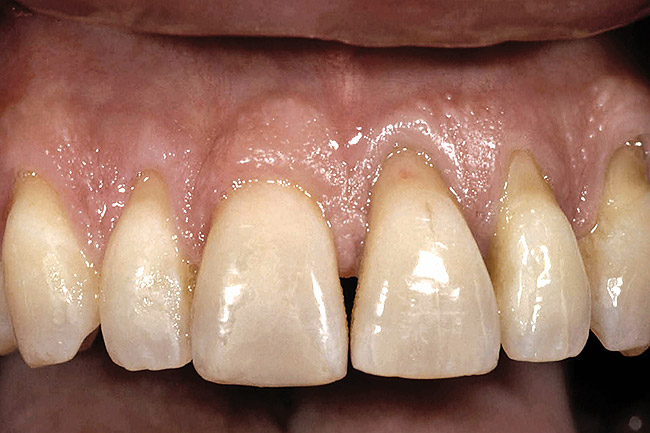

Figure 2  Between natural teeth, the average osseous scallop is 3 mm from the facial to the interproximal, and the average gingival scallop is 4.5 mm from the facial to the interproximal.

Figure 2

The real challenge when removing the two centrals is to evaluate what happens to the papilla between them after extraction.9,10 Before extraction, the osseous crest around both centrals, assuming no periodontal disease exists, roughly follows the scalloped nature of the cementoenamel junctions (CEJs) as they flow from the facial into the interproximal, resulting in an average osseous scallop of 3 mm; the average interproximal bone height is 3 mm coronal to the facial crest of bone. Because the soft tissue typically follows the scallop of the bone, the osseous scallop results in a gingival scallop of 3 mm. However, when teeth are present, an interesting phenomenon occurs. The gingiva on the facial of the tooth is positioned so that, on average, the free gingival margin is 3 mm coronal to the crest of bone. However, the interproximal papilla between teeth is positioned, on average, 4.5 mm coronal to the interproximal crest of bone, 1.5 mm, on average, more coronal to the crest of bone than is the facial tissue. This additional 1.5 mm, along with the 3 mm average osseous scallop, results in the tip of the papilla being an average 4.5 mm to 5 mm coronal to the facial free gingival margin (Figure 2).